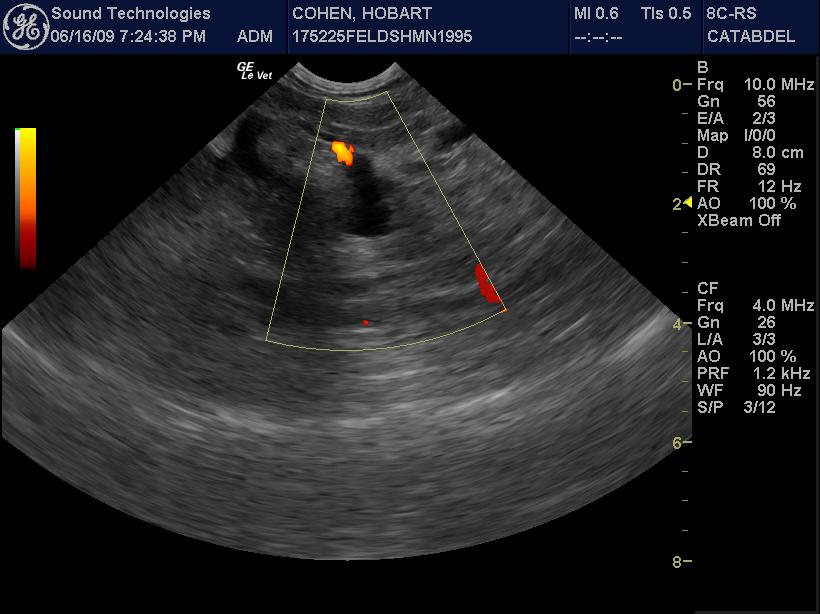

An 8-year-old MN DSH with history of hairballs (currently on Laxatone therapy), was presented for evaluation of vomiting. Abnormalities on physical examination were listlessness and mild dehydration. CBC showed leukocytosis, neutrophilia, basophilia, high MCHC, and elevated MCH. On blood chemistry hyperalbuminemia, elevated ALP and ALT activity, hypercholesterolemia, mild hyperglycemia, slight hypokalemia, and hyperbilirubinemia were evident. Blood gas analysis showed alkalosis with decreased HCO3, PCO2, and TCO2. T-4 was within normal range.

An 8-year-old MN DSH with history of hairballs (currently on Laxatone therapy), was presented for evaluation of vomiting. Abnormalities on physical examination were listlessness and mild dehydration. CBC showed leukocytosis, neutrophilia, basophilia, high MCHC, and elevated MCH. On blood chemistry hyperalbuminemia, elevated ALP and ALT activity, hypercholesterolemia, mild hyperglycemia, slight hypokalemia, and hyperbilirubinemia were evident. Blood gas analysis showed alkalosis with decreased HCO3, PCO2, and TCO2. T-4 was within normal range.

US-guided FNA of the pancreas revealed suppurative pancreatitis

Type of Imaging : Ultrasound